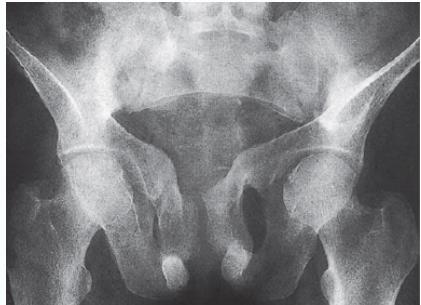

- Trefoil pelvis – acetabular protrusion

Characteristic radiological features:

- Loss of bone density.

- Thinning of the trabeculae and cortex. z

- Bone deformity. (vertebral bodies are biconcave, the femora may be bowed)